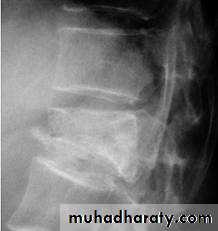

Dorsal and lumbar spine

Wedge compression fracture of a vertebral body.

The thoracolumbar junction

one or more of the vertebral bodies collapses

anteriorly and becomes wedge-shaped, giving rise to a localized kyphosis.WEDGE COMPRESSION FRACTURE

Diagnosis .

obvious symptoms and signs pointingIn cases of major fracture there will be only between the T11 and L2

Treatment

It has been shown that persistent wedging of a vertebral body is compatible. With virtually normal function.

so correction of the deformity is not essential.